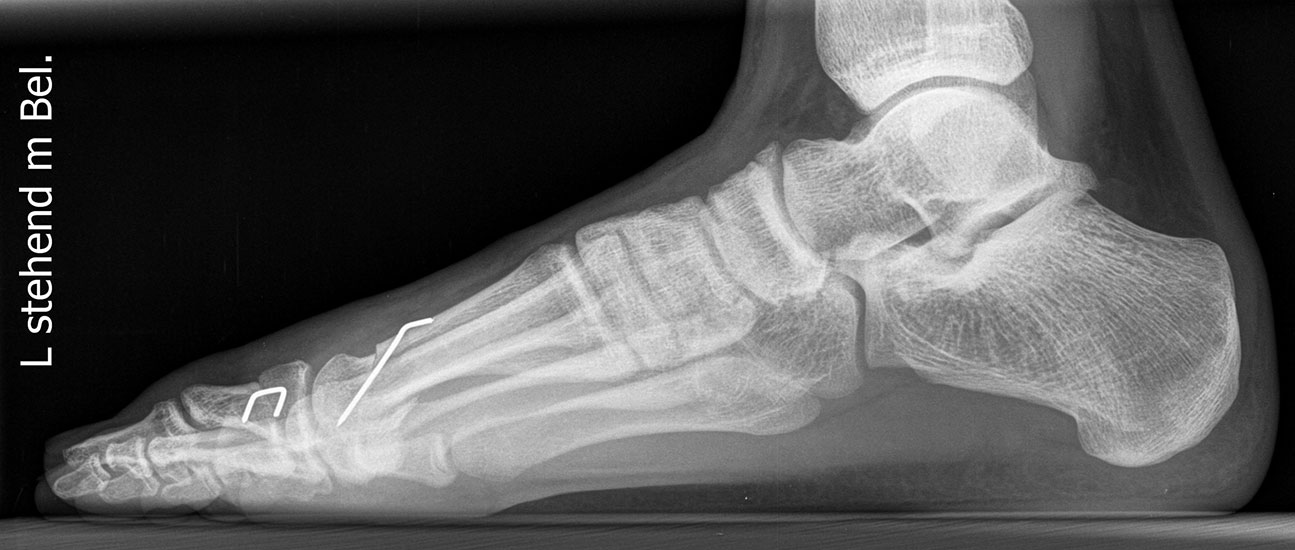

Standard ist die belastete Röntgenaufnahme des Fußes dorso-plantar und seitlich. Günstig ist eine Röhrenkippung von 10°-20°, um die Gelenke der Lisfranc-Linie einsehen zu können.

Ergänzend kann eine Schrägaufnahme hilfreich sein. Bei Metatarsalgien oder Pathologien der Sesambeine liefert die Sprinteraufnahme zusätzliche Informationen. Bei einer Pes planovalgus Fehlstellung wird ergänzend ein Saltzman view durchgeführt.

• Hallux valgus Winkel

• Hallux valgus interphalangeus Winkel

• Intermetatarsalwinkel I zu II

• Distaler Metatarsale Gelenkwinkel (PASA)

• Form des Mittelfußknochenkopfes

• Winkel Metatarsale I Basis zum Os cuneiforme mediale

• Metatarsalindex

• Elevation/ Plantarisierung I. Strahl

• Pes metatarsus adductus

• Wachstumsfugen

• Coalitiones

• Akzessorische Knochen